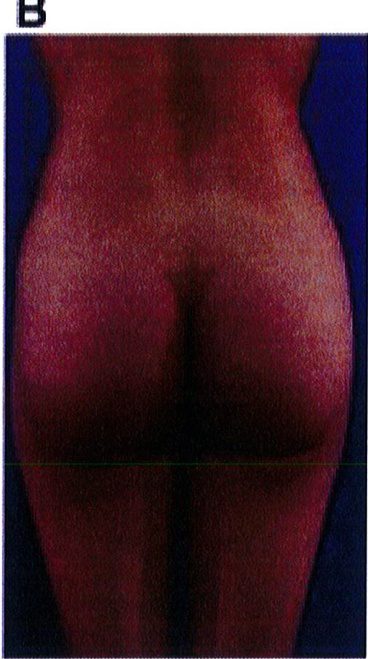

Hình. 18.. (A) Hình anh trước và (B) và sau phẫu thuật làm đầy mông của bệnh nhân được đặt khối implant dưới cân thể tích 225 mL, hai bên.

Bệnh nhân 31 tuổi tiền sử khỏe mạnh, có chỉ định nâng mông bằng implant do thiếu hụt thể tích. Hai khối anatomic implant 225 mL polyurethane dạng gel được đặt ở vị trí dưới cân. Sau phẫu thuật không ghi nhận biến chứng trong suốt quá trình hồi phục, vết mổ liền tốt (Hình 18).